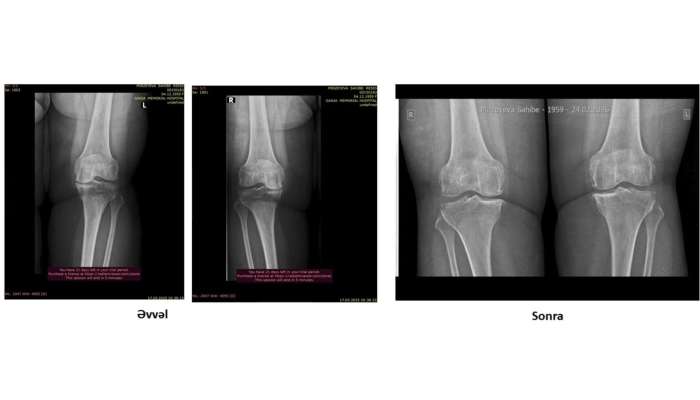

Həkimlər